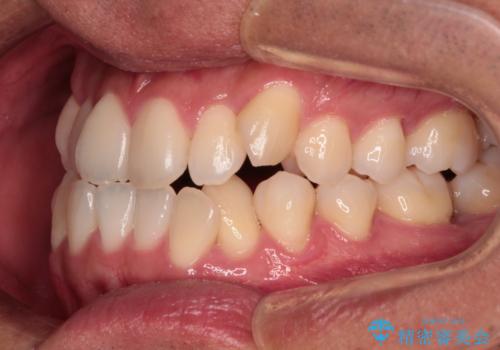

歯列弓の拡大により約1年で矯正治療を終えることができました。

正中も合わせることができ、非常にきれいに仕上がりました。